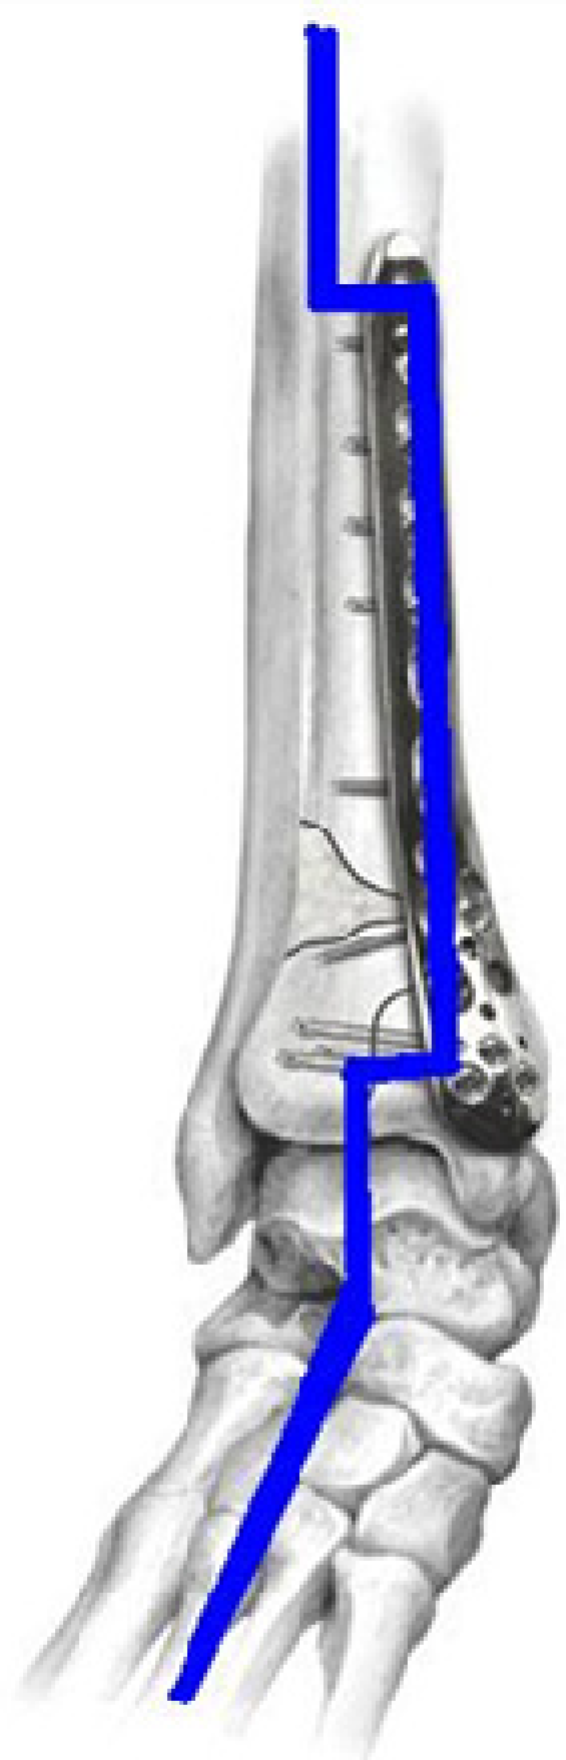

Traditional methods of osteosynthesis or osteotomy use permanent metallic implants, e.g., bone screws and bone plates made of stainless steel, titanium, cobalt alloys [8,9,10,11,12]. The conventional metallic implants are too stiff compared to bones’ moduli. The modulus mismatch between permanent implants and bones shields the healing bone from being exposed to mechanical loads. This “stress shielding” (Figure 2) results in critical clinical issues such as early implant loosening, damage healing process and adjacent anatomical structures, skeleton thickening, and chronic inflammation [13,14,15,16,17,18,19,20,21,22]. Another issue for permanent implants is that revision surgeries are necessary when the bone heals. So personal, medical (the risk of refractures and additional days of after-treatment), social and economical consequences and costs have to be performed, in which the implants are excised. Only in patients older than 60 years it is acceptable to leave metal in situ. Usually, metal implants should be removed 1 to 2 years after the first operation [11,12]. In this context, Mg-based alloys, especially Mg-Ca alloys, have received a lot of attention due to their close modulus between Mg-based alloys and bones.

Figure 2. Stress shielding in locking compression plate fixing fractures in distal tibia.